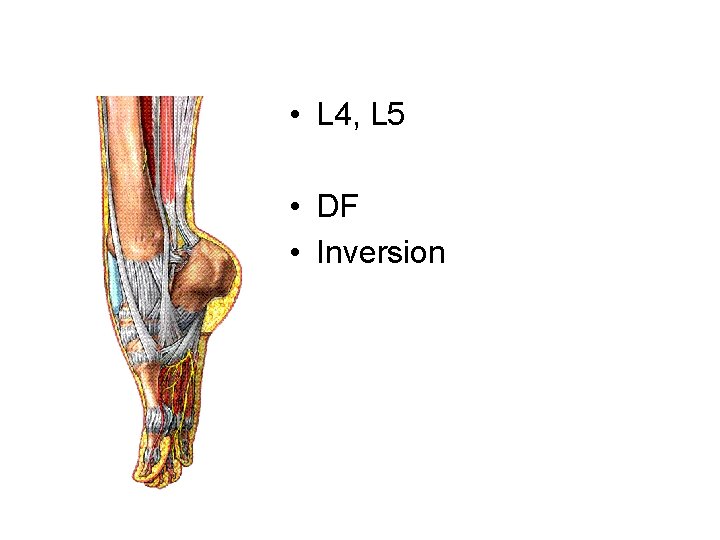

Tibialis anterior muscle

• L 4, L 5 • DF • Inversion